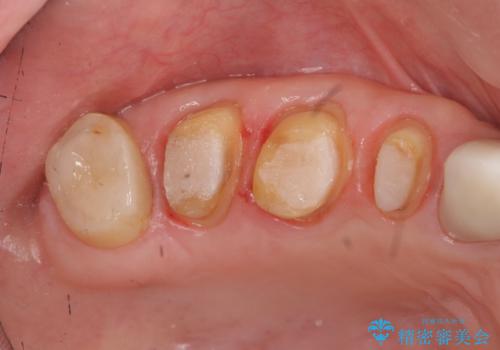

- 重度の歯ぎしり癖で歯がすり減り、見た目・噛み合わせの改善とこれ以上すり減る前の処置を希望され来院されました。

高さが短くなってしまった歯は、安定したクラウンを作るのが難しいため歯ぐきを下げる歯周外科を行ったのちに強度に優れるフルジルコニアクラウンで補綴治療を行います。

すり減ってしまった歯に対し、歯冠長延長術(歯周外科)を行うことで安定したクラウンを製作・装着することが出来ました。